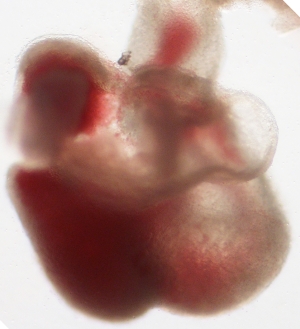

Stage

Stage:

CfS

Day:

d6